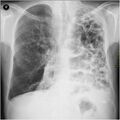

A chest X-ray is not useful to establish a diagnosis of COPD but it is of use in either excluding other conditions or including comorbidities such as pulmonary fibrosis and bronchiectasis. Characteristic signs of COPD on X-ray include hyperinflation (shown by a flattened diaphragm and an increased retrosternal air space) and lung hyperlucency.[5] A saber-sheath trachea may also be shown that is indicative of COPD.[110]

Chest X-ray demonstrating severe COPD, displaying small heart size in comparison to the lungs